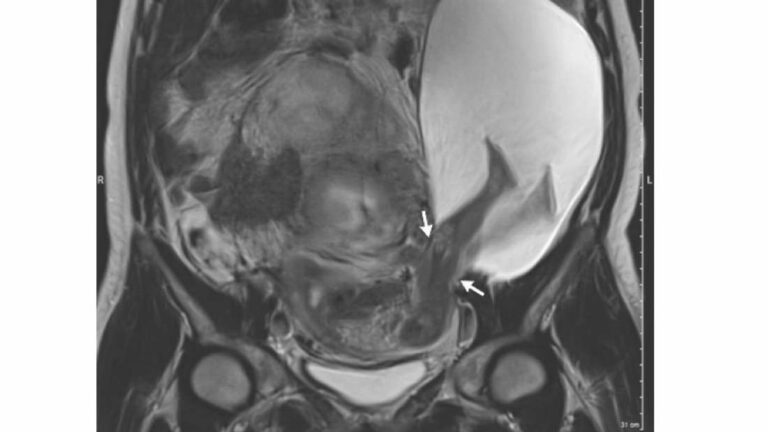

Uma ressonância magnética posterior mostrou que o útero sofrera uma ruptura de 2,5 centímetros. Desse modo o feto projetou as pernas e parte do abdômen para fora do útero da mãe.

Acontece que o bebê, então com 25 semanas de idade, causou um rompimento no útero da mãe, esticando suas pernas para a cavidade abdominal.

Contudo, durante um ultrassom de rotina, os médicos observaram o caso bizarro que aparece na capa desta matéria.